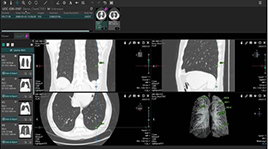

EIRL Chest CT |

・EIRL Chest CT